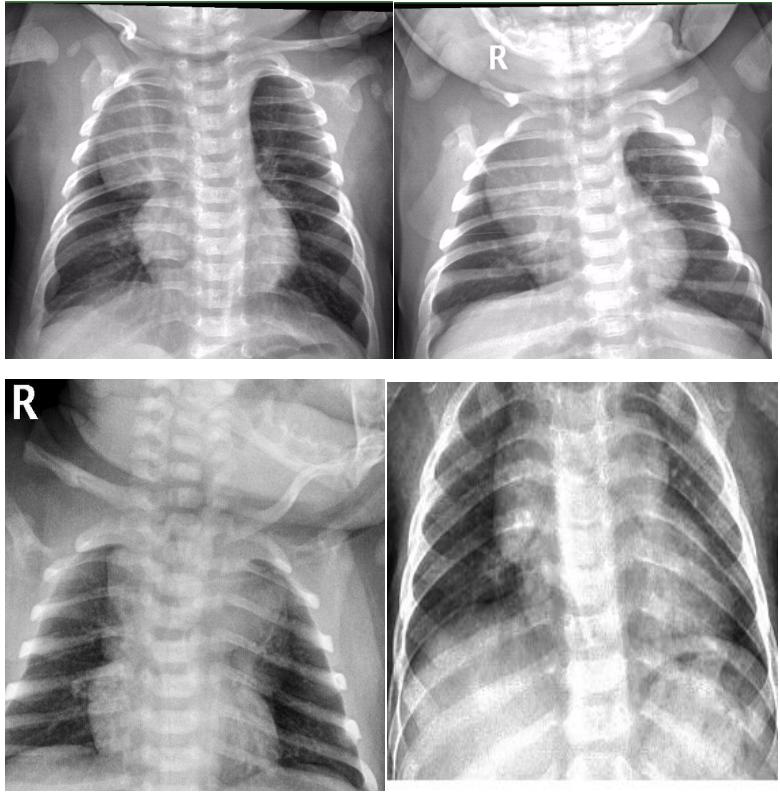

1、帆型:单侧分布,致密均匀,呈三角帆形,内缘位于纵膈内,外缘自内上斜向外下达中肺中带,边缘锐利。如下图4所示。

图4示:船帆型胸腺影

2、三角形:单侧,致密均匀,三角形尖端指向肺门,内缘与纵膈相连,下缘位于水平叶裂位置,边缘均清晰锐利。如下图5所示。

图5示:三角形胸腺影

3、条形:双侧或单侧,致密均匀,内缘与纵膈相连,下缘位于水平叶裂位置,边缘均清晰锐利。如下图6所示。

图6示:条形胸腺影.

4、圆形:一侧或双侧,致密,圆形或半圆形,内缘与纵膈无明显分界,外缘弧线清晰锐利,亦有外缘模糊。如下图7所示。

图7示:圆形的胸腺影.